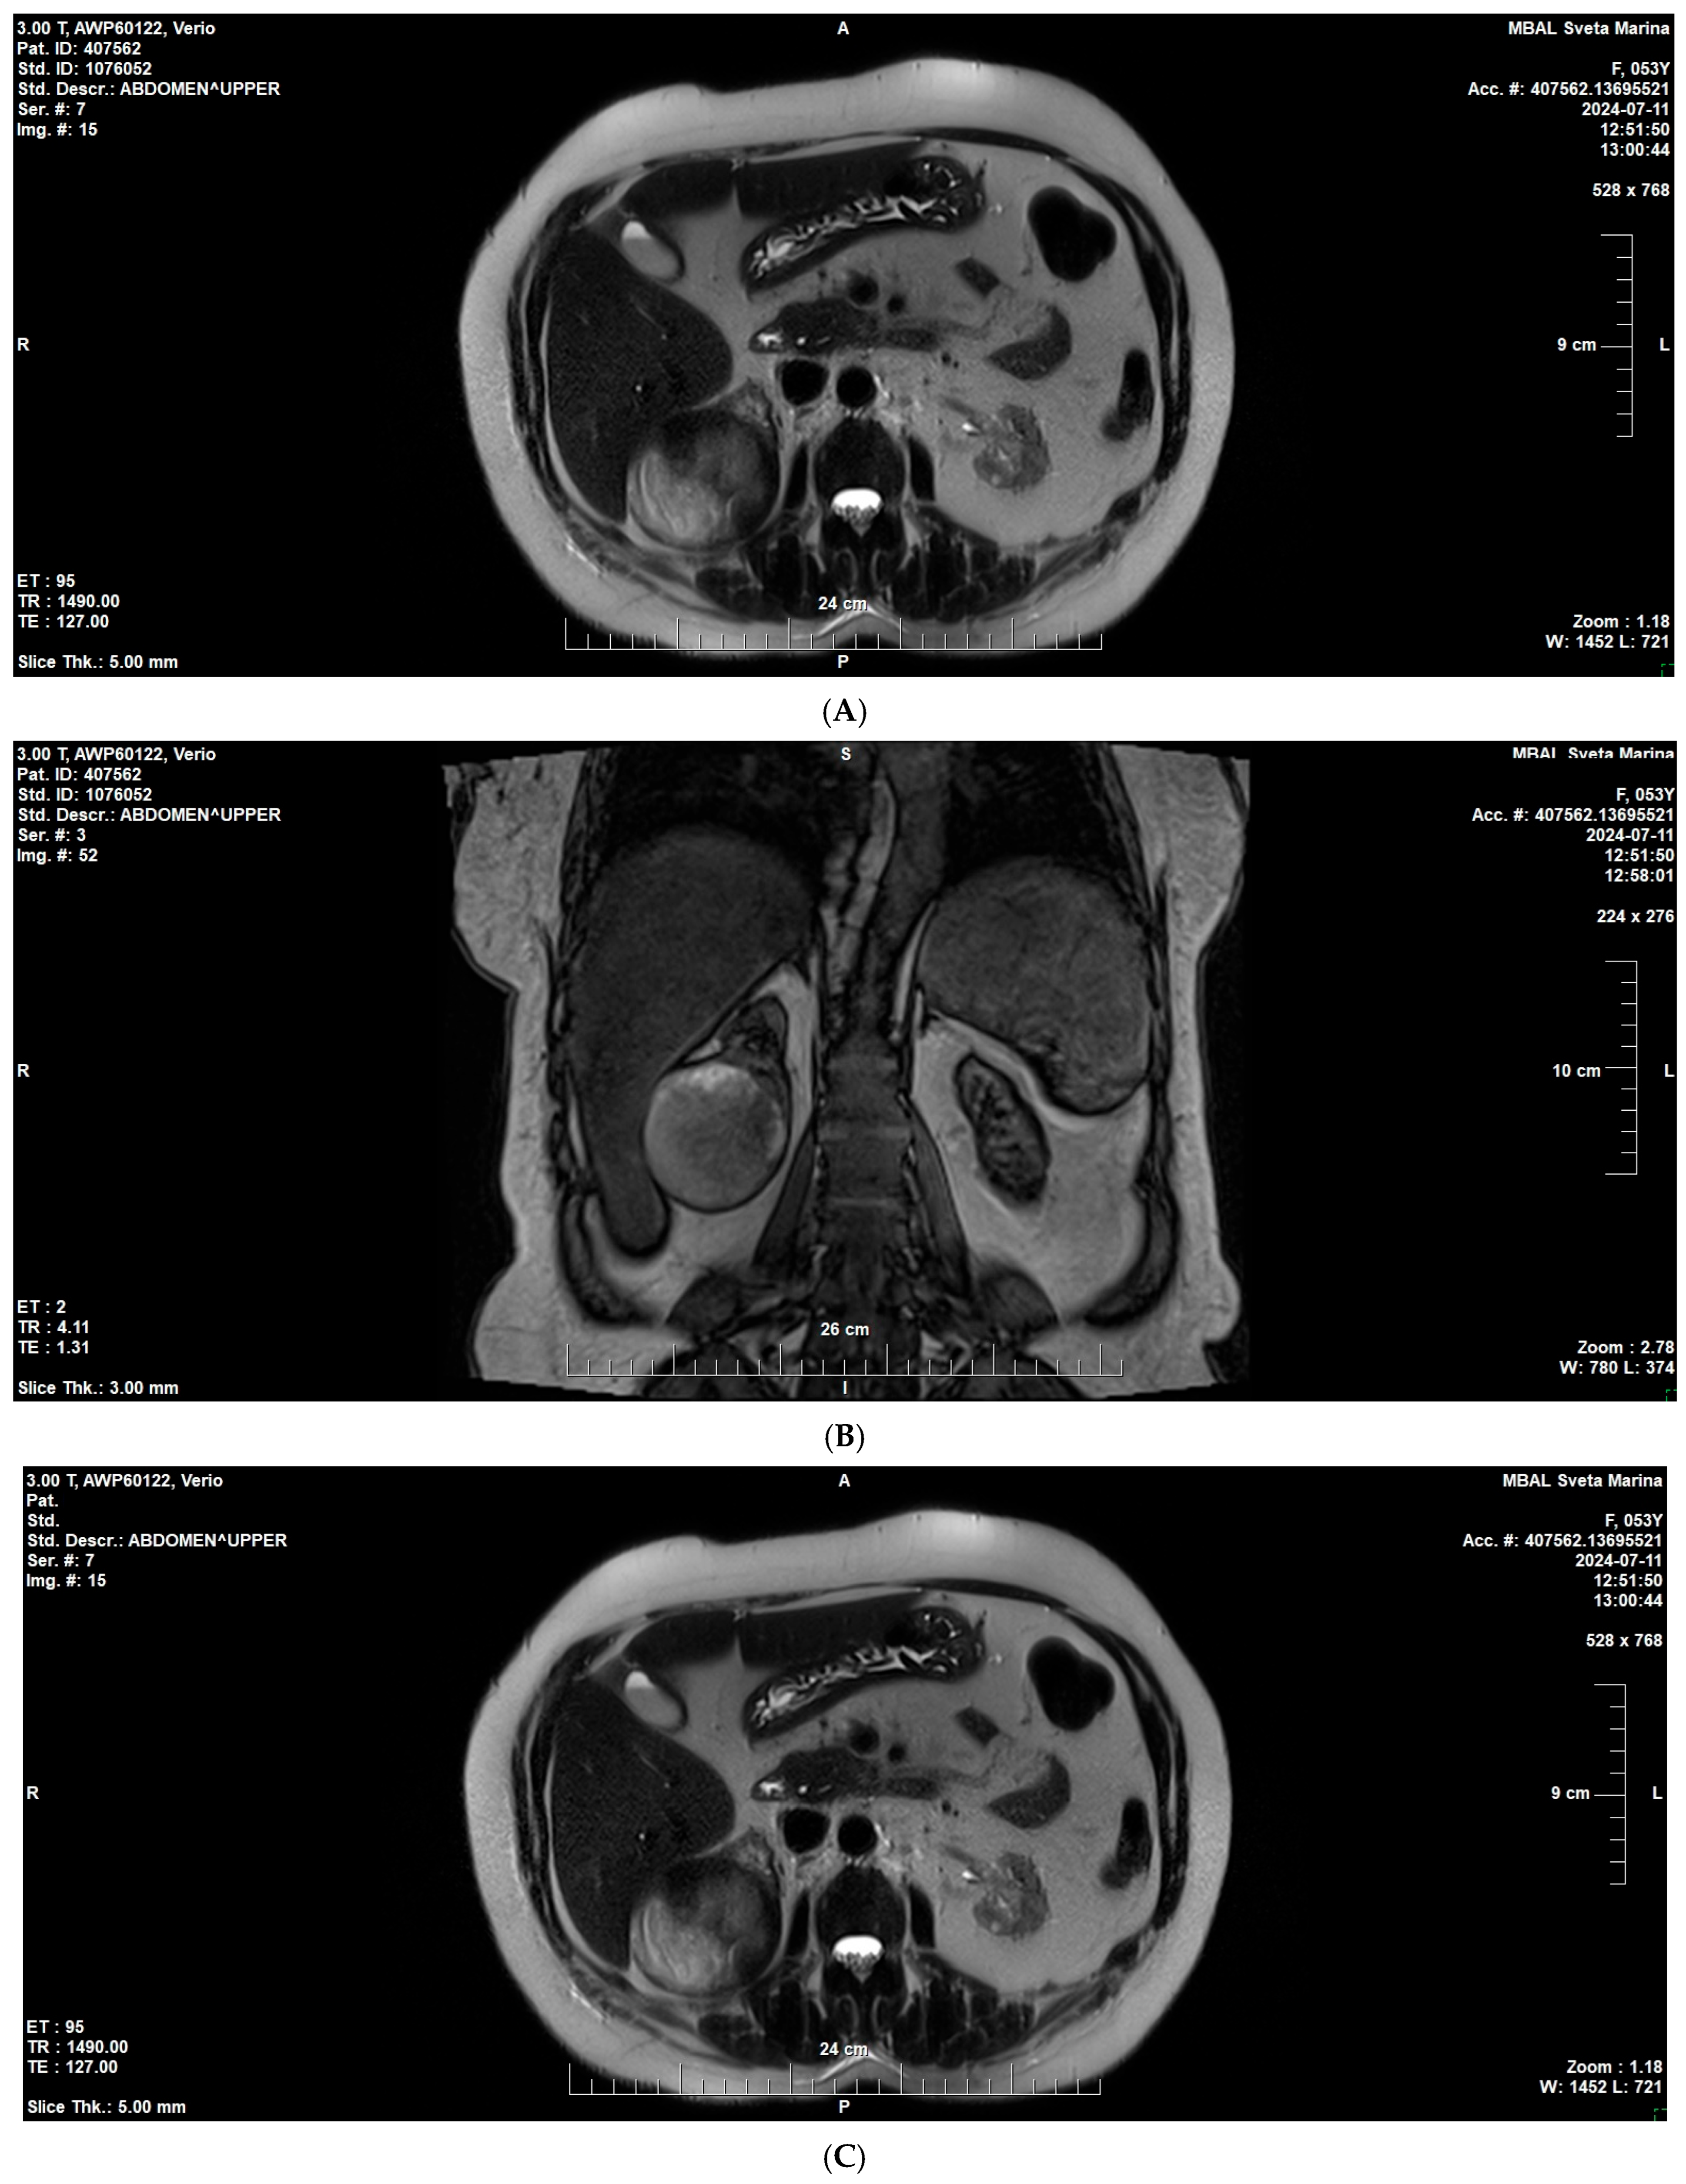

2. Case Presentation